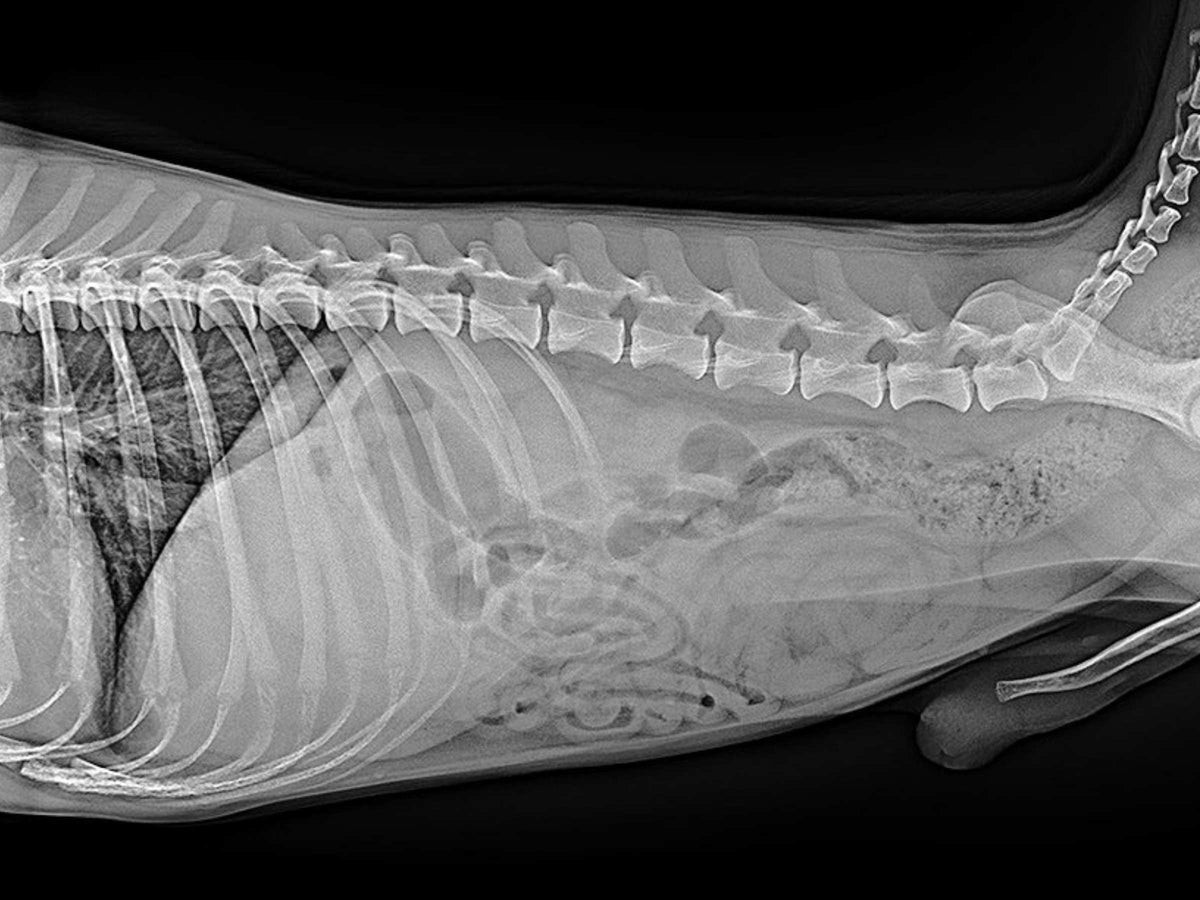

The Veterinary LG Digital X‑ray Detector is engineered for portability, durability, and high‑precision imaging across a wide range of veterinary applications. Designed with a rear‑sided handle, sculpted handgrips, and chamfered edges, it is easy to carry, position, and manoeuvre in fast‑paced clinical environments. With up to 8 hours of operating life and Hot Swap removable batteries, the detector maintains power for up to one minute during battery changes, ensuring a seamless workflow with no interruptions.

For superior diagnostic clarity, the system can be paired with a 27" 8MP IPS clinical review monitor, delivering exceptionally sharp, detailed images for confident interpretation.

Pixel size 140 μm for high‑resolution imaging

16‑bit A/D conversion for superior contrast detail

Scintillator: CsI for high sensitivity and low noise